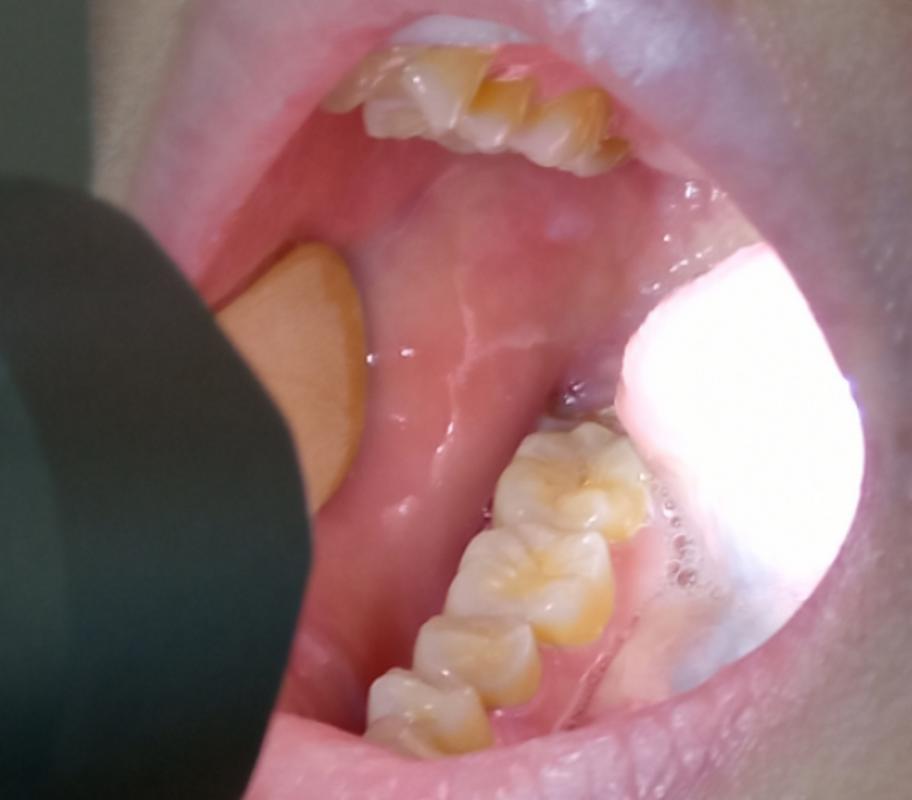

口腔内壁发白粗糙不疼是何问题?

角质化(Keratosis)或摩擦性白斑

- 描述:这是最常见的原因之一,由于牙齿不规整、假牙边缘、硬物(如薯片壳、骨头)长期、反复的摩擦刺激,导致口腔黏膜的角化层增厚,形成白色、粗糙的斑块,质地可能较硬,像一层膜。

- 特点:位置固定,通常在对应牙齿或假牙的接触区域,如果不去除刺激因素,它会持续存在。

口腔白斑病

(图片来源网络,侵删)- 描述:这是一种癌前病变,指口腔黏膜上出现的、不能用临床或病理诊断为其他疾病的白色斑块,形态多样,可以是均质型(平坦、光滑)或非均质型(粗糙、皱褶、硬结、疣状)。

- 特点:这是最需要警惕的情况,虽然大多数白斑是良性的,但有少数可能发生癌变,特别是如果白斑质地变硬、增厚、出现裂纹、溃疡或长期不消退,癌变风险会增加,吸烟、饮酒是主要的危险因素。

口腔内壁发白、粗糙不疼,最常见的原因是摩擦性白斑或白色水肿等良性问题,但也不能完全排除念珠菌感染或癌前病变(如白斑病)的可能性。

千万不要因为“不疼”就掉以轻心。 很多口腔癌的早期症状恰恰就是无痛性的白斑或溃疡,及时就医,让专业人士给出明确诊断,才是对自己健康最负责任的做法,早发现、早诊断、早处理,无论是良性病变还是癌前病变,都能得到很好的控制和治疗。